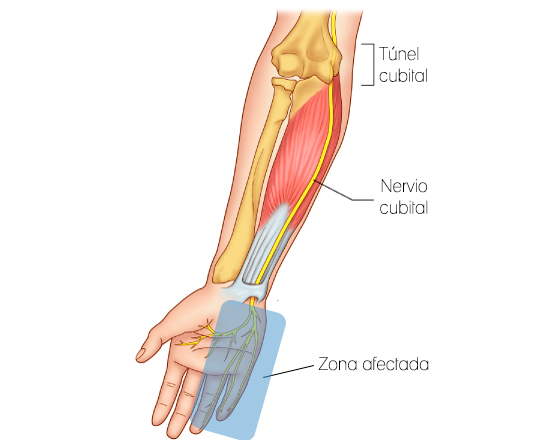

Síndrome del túnel cubital

El Síndrome del túnel cubital es a menudo causado por el uso prolongado del codo flexionado, apoyando el codo en un reposabrazos, el uso excesivo puede comprimir el nervio cubital. Se caracteriza por dolor, entumecimiento, hormigueo y problemas de sensación en los dedos meñique y anular, lateral y posterior de la mano, la pérdida de control y reducción de la fuerza de agarre.